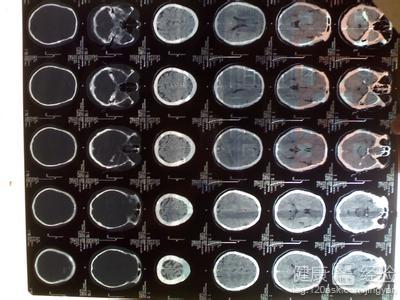

3腦血管疾病最重要的檢查是影像學檢查。CT是蛛網膜下腔出血和腦出血的首選。磁共振還是很好的反映腦部梗死的情況、CT也可以作為腦梗死的檢測。腦血管造影還可以腦部疾病的病因,必要時可行局部腦血流量(rCBF)測定。